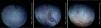

Part 1: Cross-over eye drop visitsAnalysis of the entire study cohort (baseline LLT<75nm, n=20) showed no significant increases in LLT at any time point following single-drop instillation of either the non-emollient or emollient-containing nanoemulsion eye drops. A post hoc stratification was conducted to determine if subjects with lower or higher initial LLT measurements at baseline had different effects. In the cohort of subjects with a baseline LLT<50nm (n=15), there was a significant increase in the mean LLT 15min after the nanoemulsion eye drop instillation in both the overall (8.51±13.95, p=0.03) and inferior third (9.15±14.60, p=0.03) of the measured area. For the same cohort, the mean change in LLT 15min after instillation of the non-emollient eye drop in the overall (−1.34±5.35, p=0.4) and inferior third (−1.79±7.32, p=0.4) were not statistically significant. In the cohort of subjects with a baseline LLT ≥50nm (n=5), no significant changes in mean LLT occurred with use of the nanoemulsion or non-emollient eye drop at any time point following single-drop instillation. Table 1 summarizes the changes in LLT 15min following single-drop instillation of both the nanoemulsion and non-emollient eye drops, as well as the significance at this time point for each cohort. No significant increase in LLT occurred for either drop at any time point beyond 15min for any cohort examined, and therefore, LLT measurements made beyond 15min are not presented in Table 1. Fig. 2 contains images of the lipid layer collected from a single subject at baseline and 15min after instillation each of the study eye drops.

Stroboscopic video color microscope (SVCM) images taken from an individual subject who best represented average LLT at baseline and 15min post-instillation of the emollient and non-emollient eye drops in the lower LLT (<50nm) cohort. (A) Baseline image taken prior to drop instillation. (B) Image taken 15min following instillation of the non-emollient eye drop. (C) Image taken 15min following instillation of the nanoemulsion eye drop. The brighter colors correspond to a thicker lipid layer as depicted on the key to the right of each image.